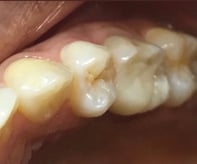

Escaneamento da gengiva e posição do implante

Desenho Digital em Laboratório

Coroa sobre Implante aparafusada em Modelo impresso. zirconia/cerâmica

Coroa instalada em boca